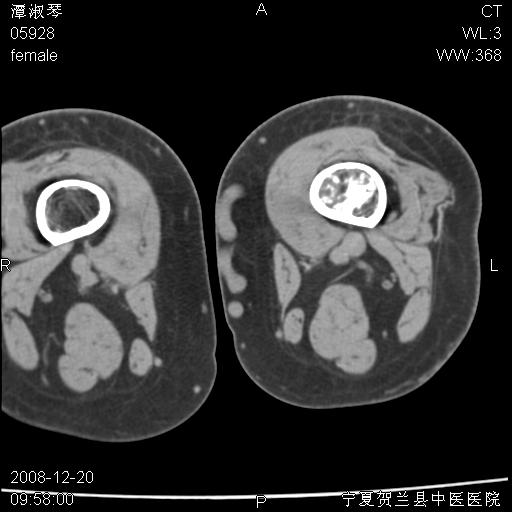

标题: CT17526:请各位看看是啥? [打印本页]

标题: CT17526:请各位看看是啥?

内生软骨瘤?骨梗死?

考虑内生软骨瘤可能性大

考虑-----骨梗死+退变

支持骨梗死,退行性骨关节病,膝关节积液.

考虑骨梗死可能性大

支持骨纤或内生软骨瘤或骨梗死,退行性骨关节病,膝关节积液.

骨梗死可能性大

左股骨下段骨梗死。双膝退变。

支持:内生软骨瘤或骨梗死!另:退行性骨关节病,膝关节积液。

左胫骨下端松质骨及髓腔内可见点片状高密度灶,骨皮质无明显膨胀及变薄。病变范围较长。支持骨梗死,退行性骨关节病,膝关节积液